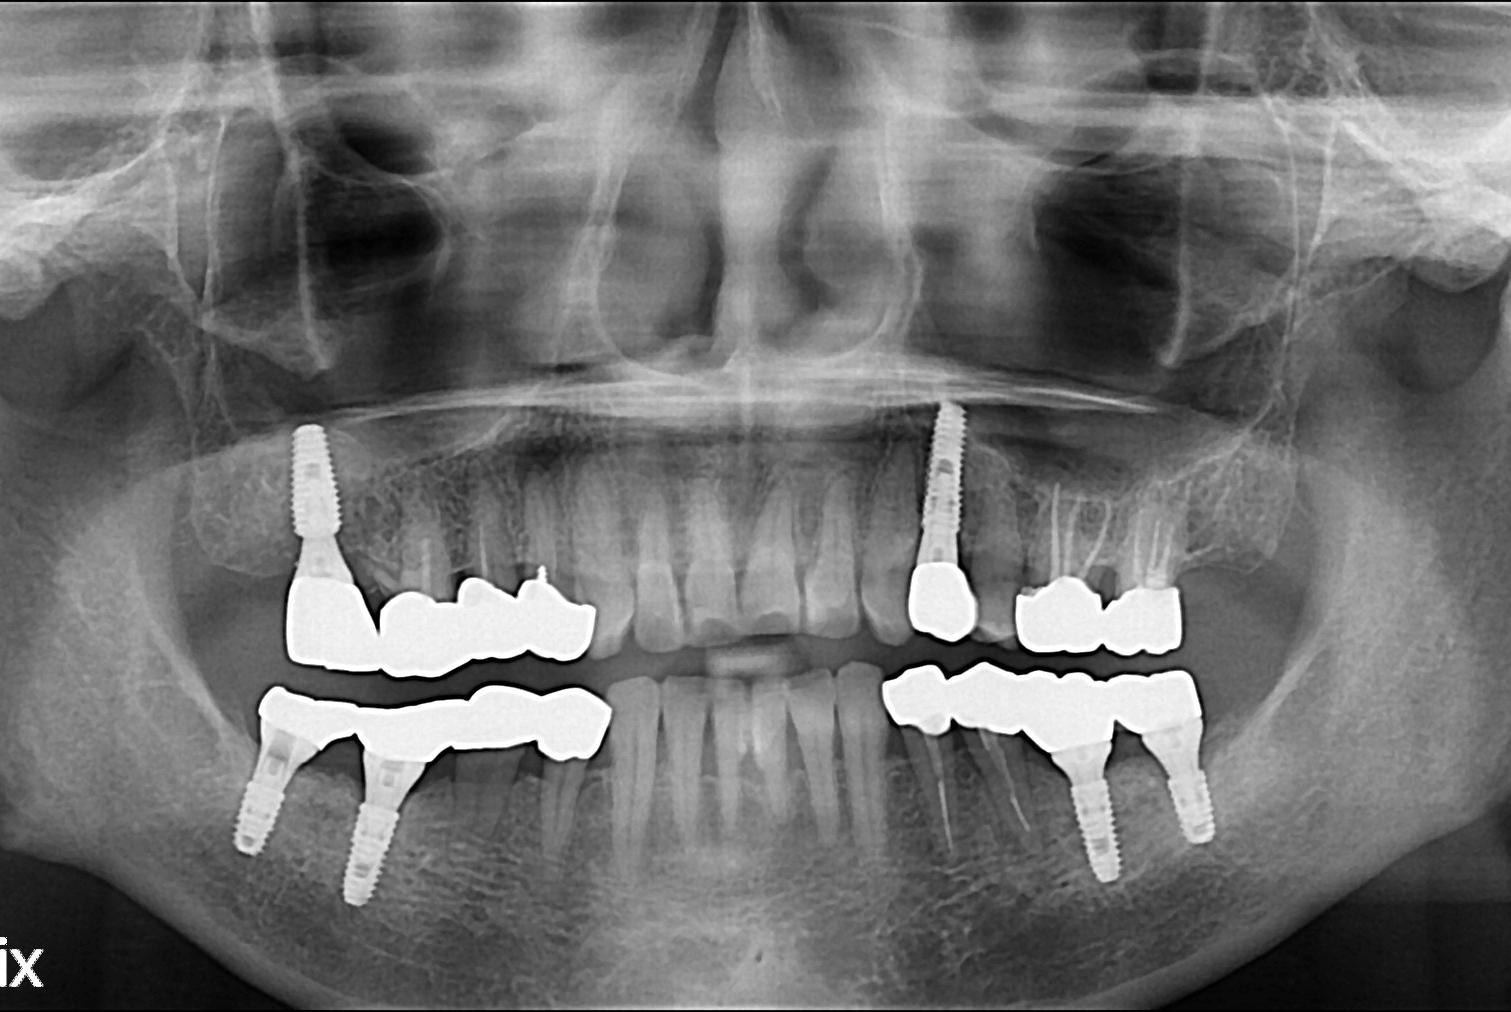

치료전 : 2016-08-26

치료후 : 2016-12-14

세종치과는 많은 환자와 다양한 케이스를 바탕으로 항상 편안한 임플란트 수술을 제공하고자 노력하고,

오래동안 튼튼히 쓸 수 있는 임플란트 수술을 가장 큰 목표로 삼고 있습니다